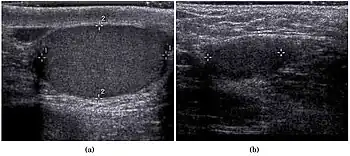

Teratoma Although teratoma is the second most common testicular tumor in children, it affects all age groups. Mature teratoma in children is often benign, but teratoma in adults, regardless of age, should be considered malignant. Teratomas are composed of all three germ cell layers, i.e. endoderm, mesoderm and ectoderm. At ultrasound, teratomas generally form well-circumscribed complex masses. Echogenic foci representing calcification, cartilage, immature bone and fibrosis are commonly seen [Fig. 5]. Cysts are also a common feature and depending on the contents of the cysts i.e. serous, mucoid or keratinous fluid, it may present as anechoic or complex structure [Fig. 6].

Fig. 5. Teratoma. A plaque-like calcification with acoustic shadow is seen in the testis.

Fig. 6. Mature cystic teratoma. (a) Composite Image. Mature cystic teratoma in a 29-year-old man. Longitudinal sonography image of the right testis shows a multilocular cystic mass. (b) Mature cystic teratoma in a 6-year-old boy. Longitudinal sonography of the right testis shows a cystic mass containing calcification with no obvious acoustic shadow.